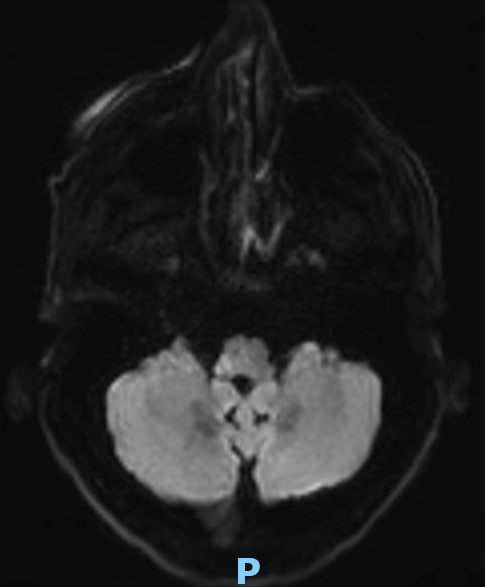

Le type d’hémianopsie est très important car il permet de localiser une atteinte neurologique, en connaissant le trajet des voies optiques.

Figure d’après le Collège des enseignants de neurologie (CEN). Altération aiguë de la vision.

Cette question supposait d’avoir bien en tête le schéma des voies optiques, et d’avoir des repères sur les principaux territoires vasculaires cérébraux et l’atteinte clinique associée. Il bien mentionné par le CEN que l’hémianopsie latérale homonyme gauche peut se voir dans un AVC sylvien superficiel droit.